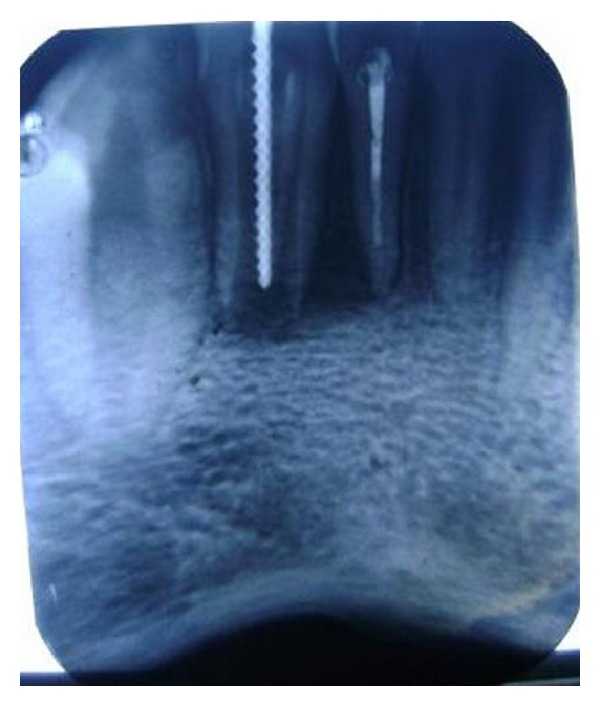

A diagnostic periapical radiograph revealed that 32 presented with dens in dente type II with immature apex and periapical radiolucency of approximately 15 mm × 20 mm extending distal to the root tip of tooth number 31 [Figure 3]. Another radiograph was taken with a gutta percha point placed through the sinus (through and through connection). Endodontic treatment of the involved teeth (31 and 32) was the plan of treatment [Figure 4].

Figure 3.

Initial radiograph showing DI type II with immature apex in relation to 32 and periradicular lesion associated with 31 and 32.